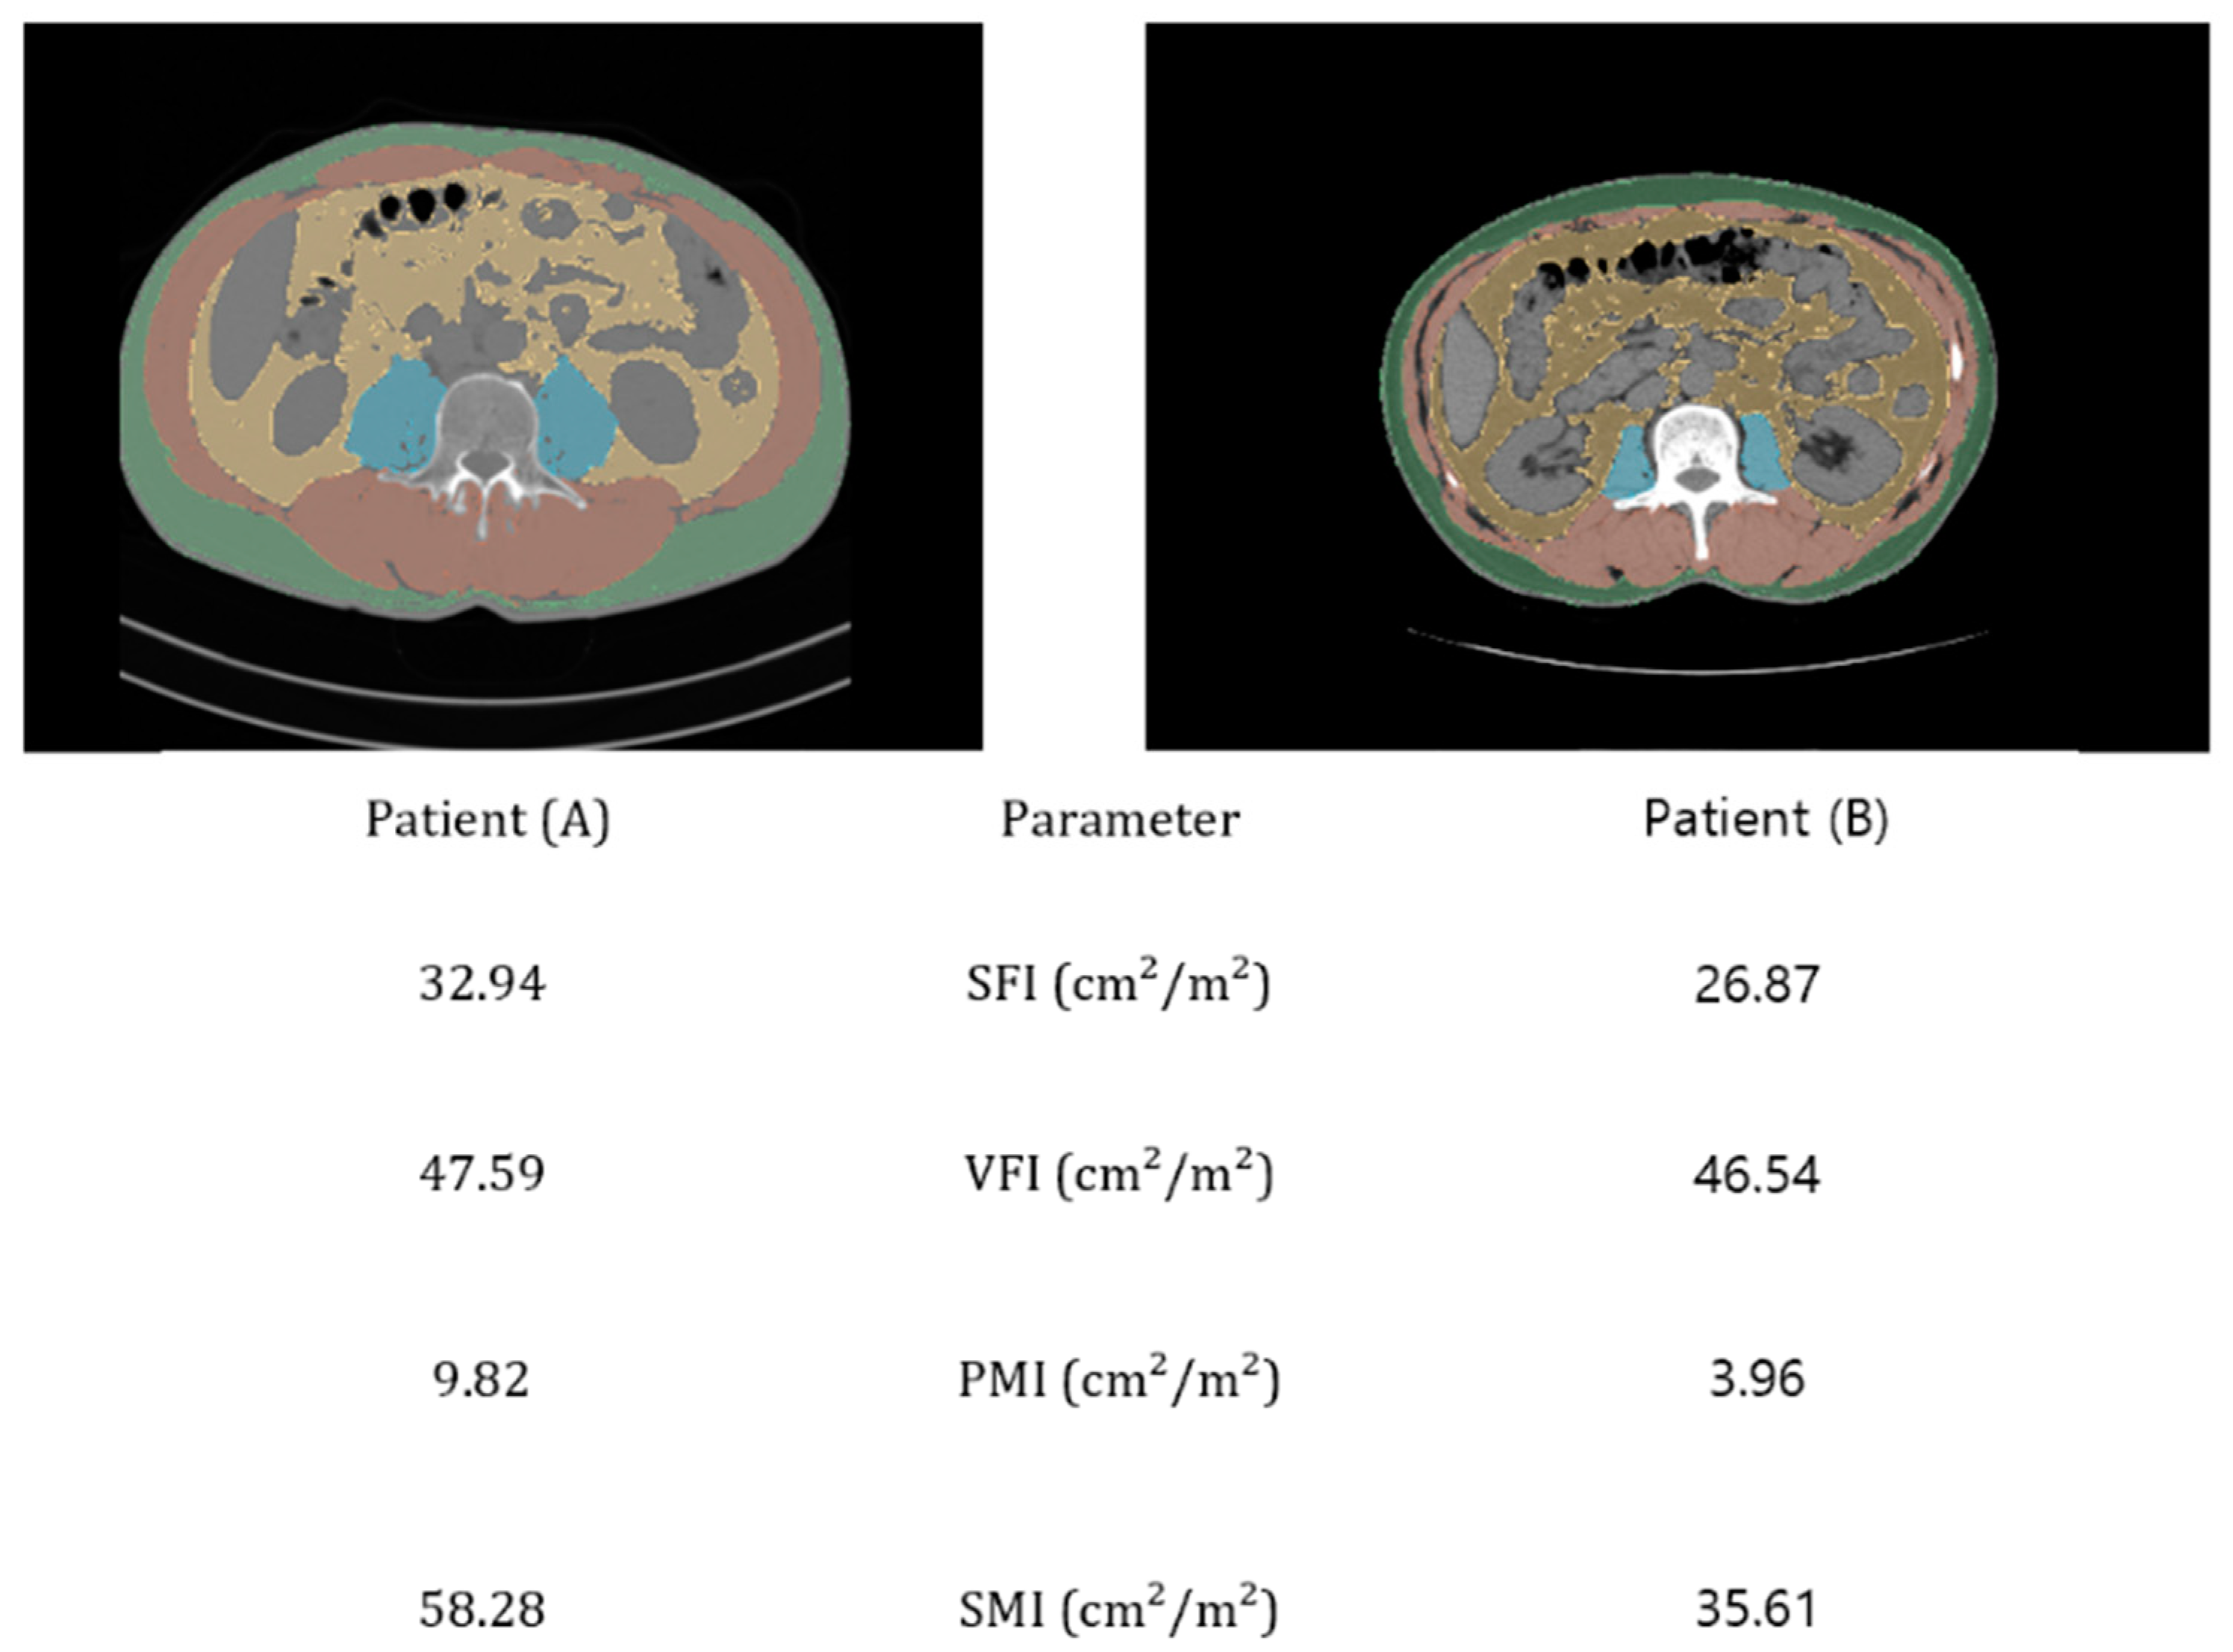

2.3. Body Composition Assessment

| SFA (cm2) | 121.33 ± 59.84 | 115.57 ± 59.92 | 104.98 ± 46.81 | 116.10 ± 57.48 | |

| VFA (cm2) | 136.38 ± 79.83 | 91.44 ± 56.05 | 63.17 ± 49.66 | 105.84 ± 72.17 | |

| PMA (cm2) | 18.52 ± 4.58 | 14.14 ± 3.30 | 10.60 ± 4.66 | 15.40 ± 5.14 | |

| SMA (cm2) | 126.81 ± 19.23 | 105.01 ± 15.48 | 80.45 ± 17.99 | 125.33 ± 28.51 | |

| VFI (cm2/m2) | 49.38 ± 27.97 | 34.36 ± 21.07 | 24.94 ± 19.95 | 39.18 ± 25.86 | |

| SFI (cm2/m2) | 44.24 ± 20.50 | 44.26 ± 25.67 | 41.46 ± 19.68 | 43.72 ± 22.26 | |

| PMI (cm2/m2) | 6.79 ± 1.46 | 5.24 ± 1.06 | 4.07 ± 1.55 | 5.70 ± 1.70 | |

| SMI (cm2/m2) | 53.39 ± 6.25 | 44.23 ± 5.15 | 35.17 ± 6.17 | 46.54 ± 9.01 | |